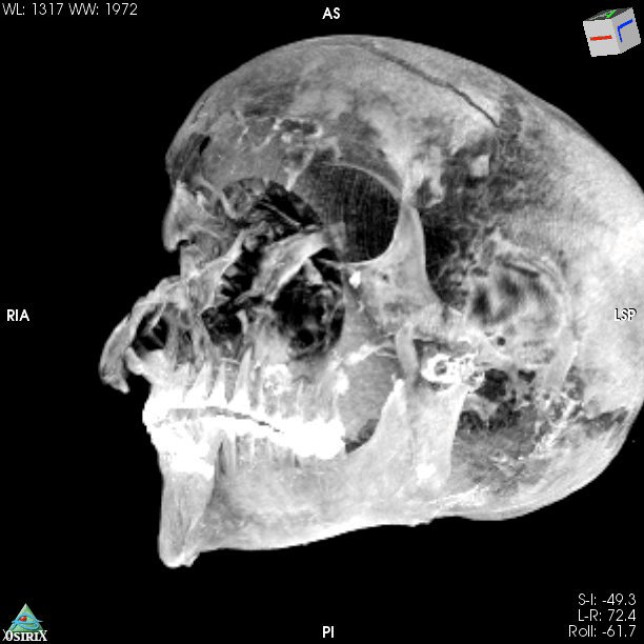

一开始不少专家都认为塞克嫩拉可能是在宫殿睡觉时被刺客杀害,但始终未有更详尽的证据,让学界对他的死因争论不休。不过开罗大学(Cairo University)放射学教授萨利姆(Sahar Saleem)与研究团队利用电脑断层扫描,发现防腐剂巧妙地掩盖头骨右侧的其他伤口,加起来总共有5个大大小小的伤口,包括额头上一道横切伤、右眉上方、左眼下方及左耳下都有伤痕,右眼窝骨头则被钝器砸碎,身体则没有受伤。

研究中也分析5种不同的西克索人武器,并与塞克嫩拉的伤口进行匹配。萨利姆表示,武器中包括包括战斧、长矛和3种不同的匕首,塞克嫩拉很可能是在仪式中被处决,因为通常一般执行处决时,刽子手只会从同一角度执行,鲜少以不同角度、不同武器进行5次攻击,且考量到木乃伊保存状况较差,显见防腐过程处理匆促,且并非在皇家木乃伊工作坊完成。